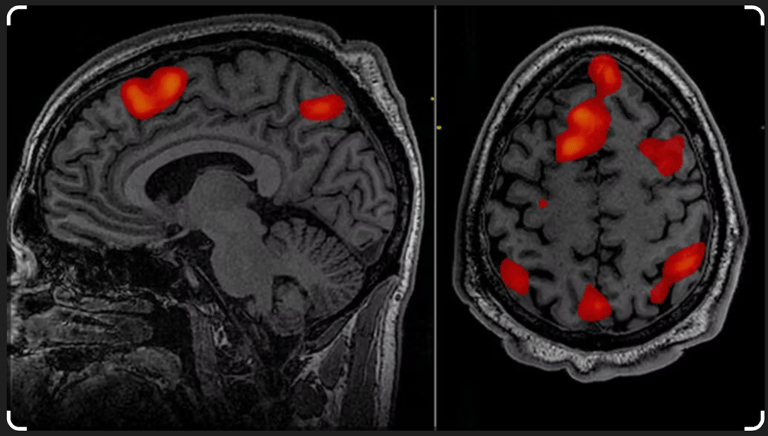

Published in the journal Nature by psychiatrists at Weill Cornell University. Functional magnetic resonance imaging (fMRI) scanners were used to compare the brain activities of clinically depressed and healthy people.